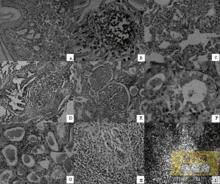

病理變化

PDNS的組織病理學變化PDNS的組織病理學變化

過去:腎臟呈現腎小球腎炎和間質性腎炎。部分豬腎臟腫大,表面有白色壞死灶,有點狀出血或淤血點。淋巴結腫大,特別是腹股溝淋巴結腫大3~4倍。有時可見黃色胸水或心包積液。脾臟輕微腫大,有出血點。肝臟呈桔黃色,心肌肥大。偶見胃潰瘍。

現在:尚有大腸和小腸黏膜充血、出血,肺出血。膀胱、輸尿管積尿。細菌感染時,可見心包炎、胸膜炎、腹膜炎、關節炎等病變。且常與肺炎支原體、PRRS、豬瘟等並發感染,導致病變複雜多樣。

病理學診斷

當發現全身淋巴結腫大,肺退化不全或形成固化、緻密病灶時,應懷疑本病。病理組織學檢查可見全身淋巴組織的淋巴細胞減少,單核吞噬細胞類細胞浸潤及形成多核巨細胞,如在這些細胞中觀察到嗜鹼性或兩性染色的細胞質內包涵體,則基本可以確診。